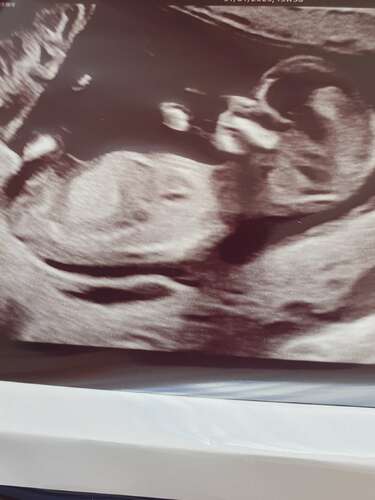

Ik had in deel 25 al een foto geplaatst van mijn laatste echo (andere dan deze), ik was toen 12 weken zwanger. Nu had ik het idee dat deze foto misschien wat duidelijker was. Ik vraag me af wat wat is. Wat denken jullie?? 😁

Ik ben heel benieuwd! Wat denken jullie?

Meisje

Jongen

Helaas niet te zien